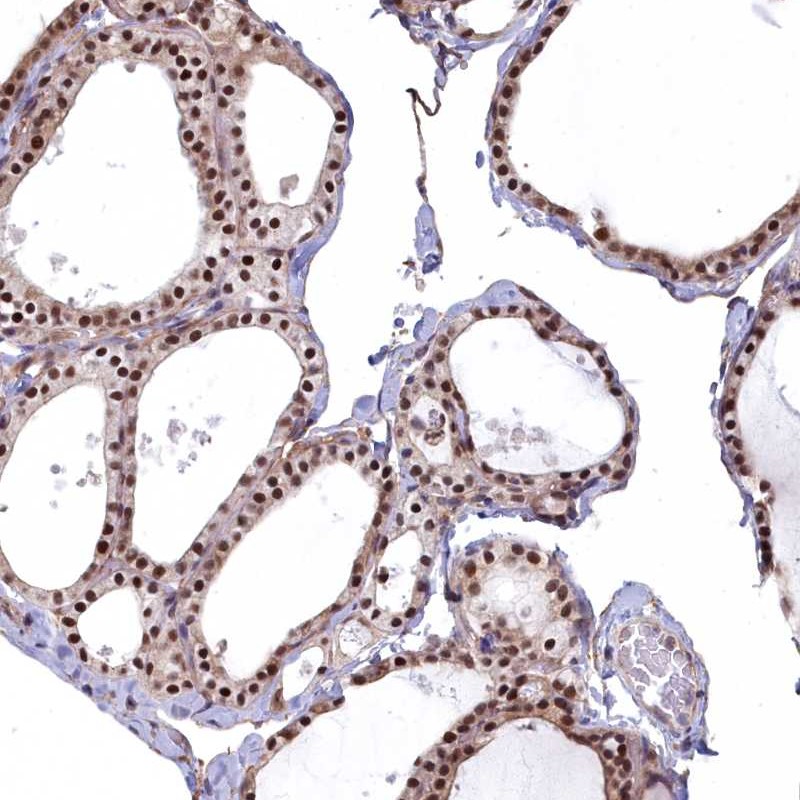

Immunohistochemical staining of human thyroid gland shows strong nuclear positivity in glandular cells.